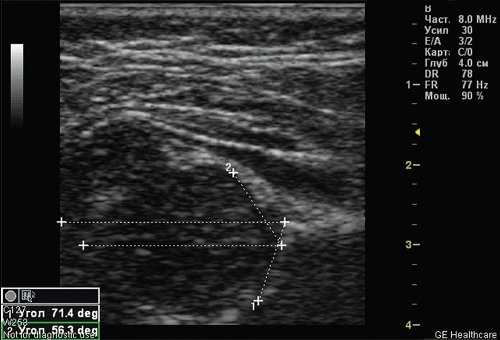

Тип 2б тазобедренных суставов выявлен у 25 (6,33%) детей - дисплазия тазобедренных суставов у детей старше 3 мес (рис. 4). Костная вертлужная впадина недостаточно развита, костный эркер закруглен, костнохрящевое соотношение меньше 2/3, хрящевая часть крыши охватывает головку бедренной кости. Угол α меньше 59°, но больше 50°, угол β больше 60°.

Рис. 4. Тазобедренный сустав тип 2б.

1 - угол α=53,4°;

2 - угол β=62,6°.